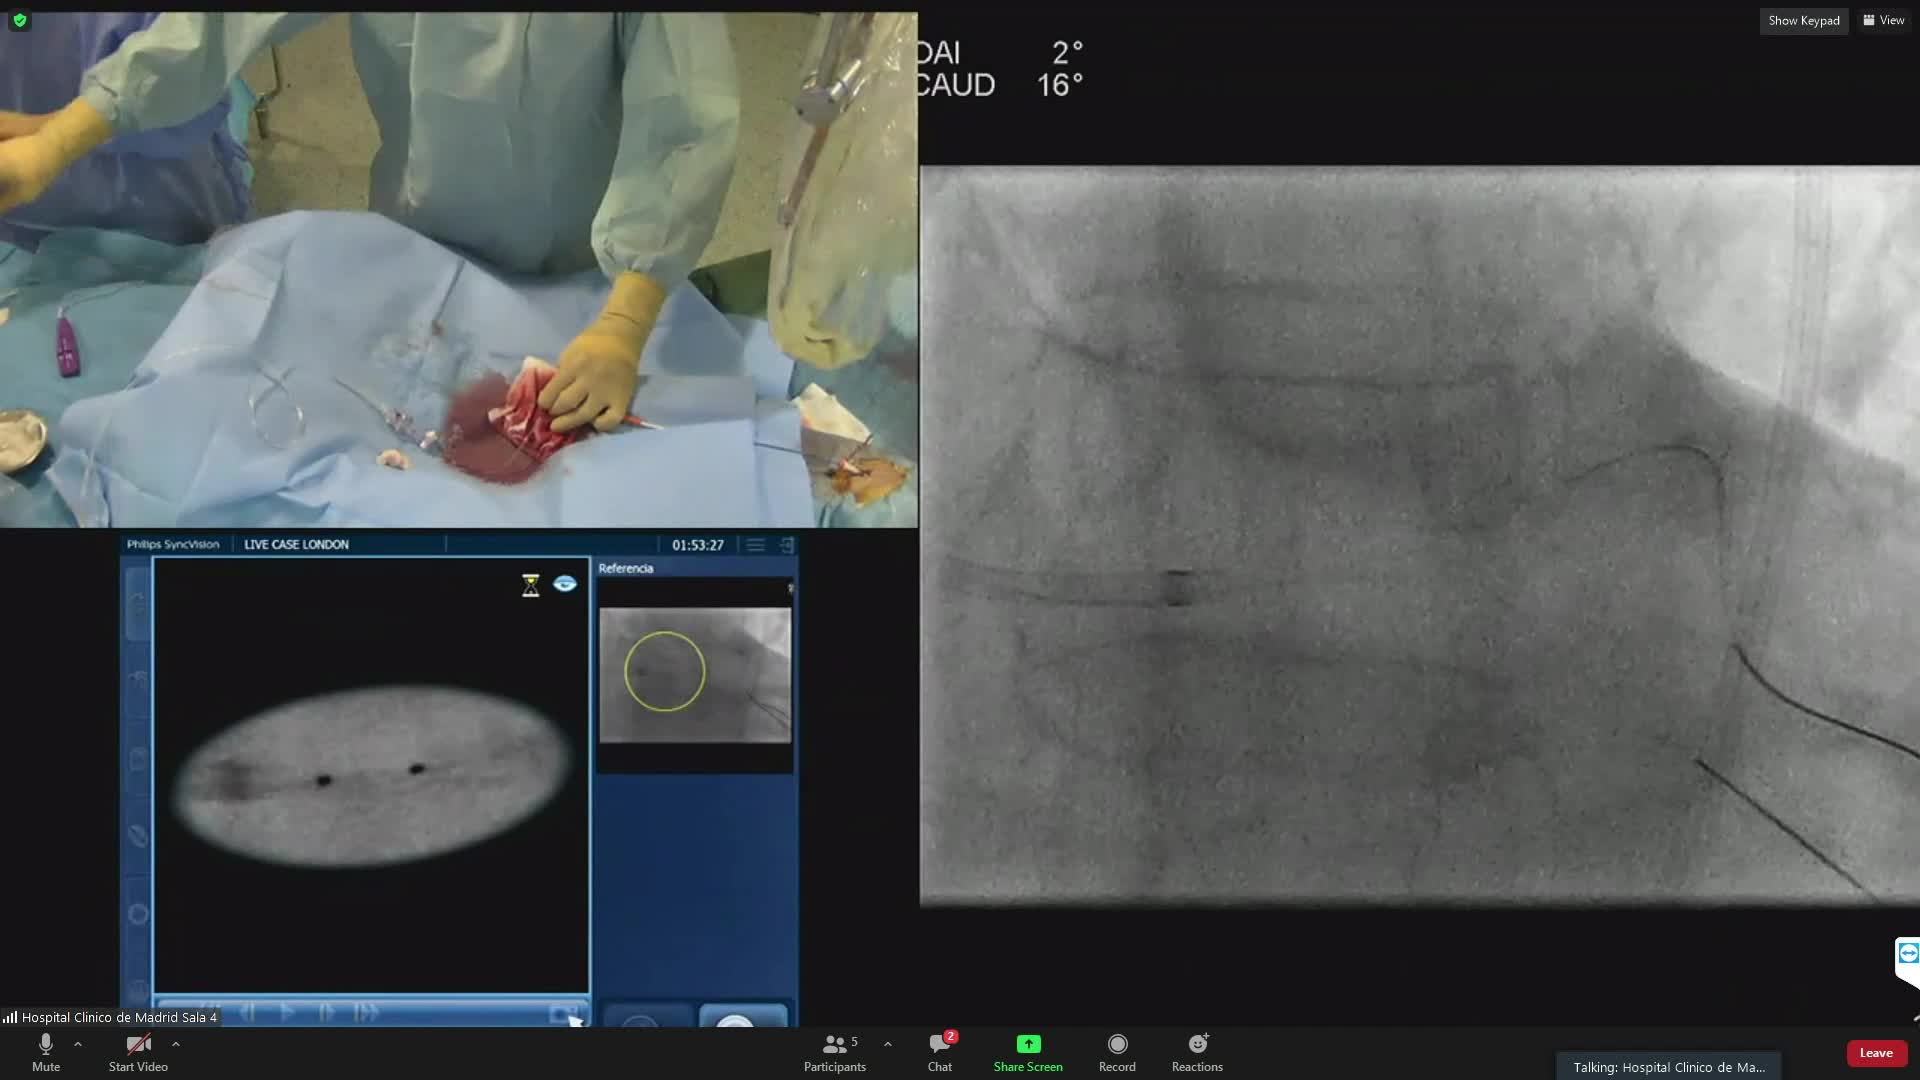

Prof Javier Escaned is Head of Section (Interventional Cardiology Section) at Hospital Clinico... Prof Javier Escaned is Head of Section (Interventional Cardiology Section) at Hospital Clinico San Carlos / Complutense University (Madrid, Spain). He trained in the United Kingdom as Specialist in Cardiology and obtained his PhD in The Netherlands. Author of >700 indexed scientific articles on interventional cardiology, imaging and physiology (h-index 100) and over 30 years of experience as PCI operator, he regularly lectures and performs live cases at major scientific and educational meetings. He is a recipient of the European Society of Cardiology (ESC) Silver Medal and the Andreas Grüntzig Award for his contributions to the fiedl fo Interventional Cardiology. Main areas of expertise include complex PCI, intracoronary diagnostics and functional coronary angiography. His track record in coronary physiology comprises being investigator on pioneer FFR trials like DEFER (1998), collaborator with Justin Davies in the validation and clinical implementation of iFR, and developer of new tools for the assessment of coronary microcirculation. Editorial roles include Deputy Editor EHJ, Advisory Editor Eurointervention, editor of the textbooks “Coronary Stenosis: Imaging, Structure and Physiology” and “Physiological Assessment of Coronary Stenoses and the Microcirculation". Recent board positions include EAPCI board / Education Committee Chair, ESC WG Coronary Pathophysiology and Microcirculation, EuroCTO Board. Recent trials as Principal Investigator include ADVISE II, DEFINE FLAIR, SYNTAX II, PIONEER IV, Cerebral-Coronary-Connection (C3), DCR4Contrast, INOCA LongCovid and AID ANGIO. Additional interests are philosophy and music.